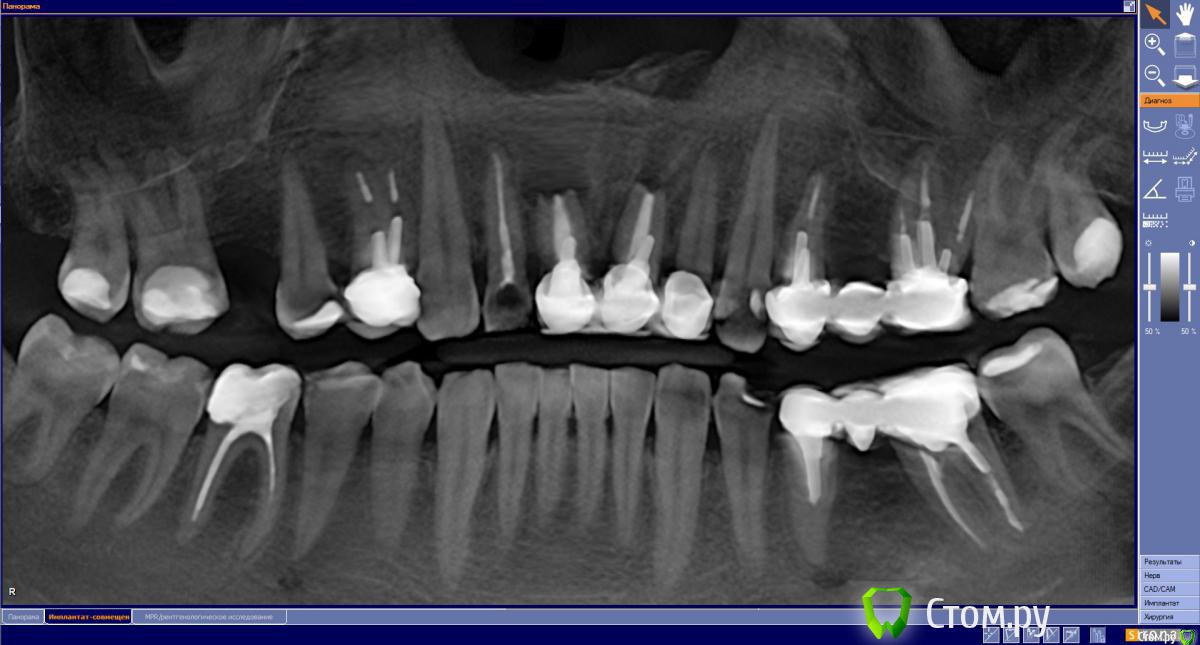

Sergei27 Опубликовано 17 мая, 2015 Поделиться Опубликовано 17 мая, 2015 (изменено) Мне 40 лет 1.1 и 2.1 травма 29 лет назад, повторные кисты после резекции 16 лет назад. 1.2 и 2.2 уже депульпированы и подготовленны под временный мост. Планируемый план лечения:1 день:Удаление 1.1 и 2.1 (была опечатка, исправил)Cerabone 0.5млУстановка импл. NeoBioTech (Ю.Корея)4 день: Слепок и временный мост на двойки.60-180 ? день:Установка постоянных коронок 1.2 1.1 2.1 2.2 Вопрос: Правильно ли выбран план лечения?Предыдущий план предполагал удаление и костную пластику, и после 6 мес имплантацию. Изменено 17 мая, 2015 пользователем Sergei27 Ссылка на комментарий